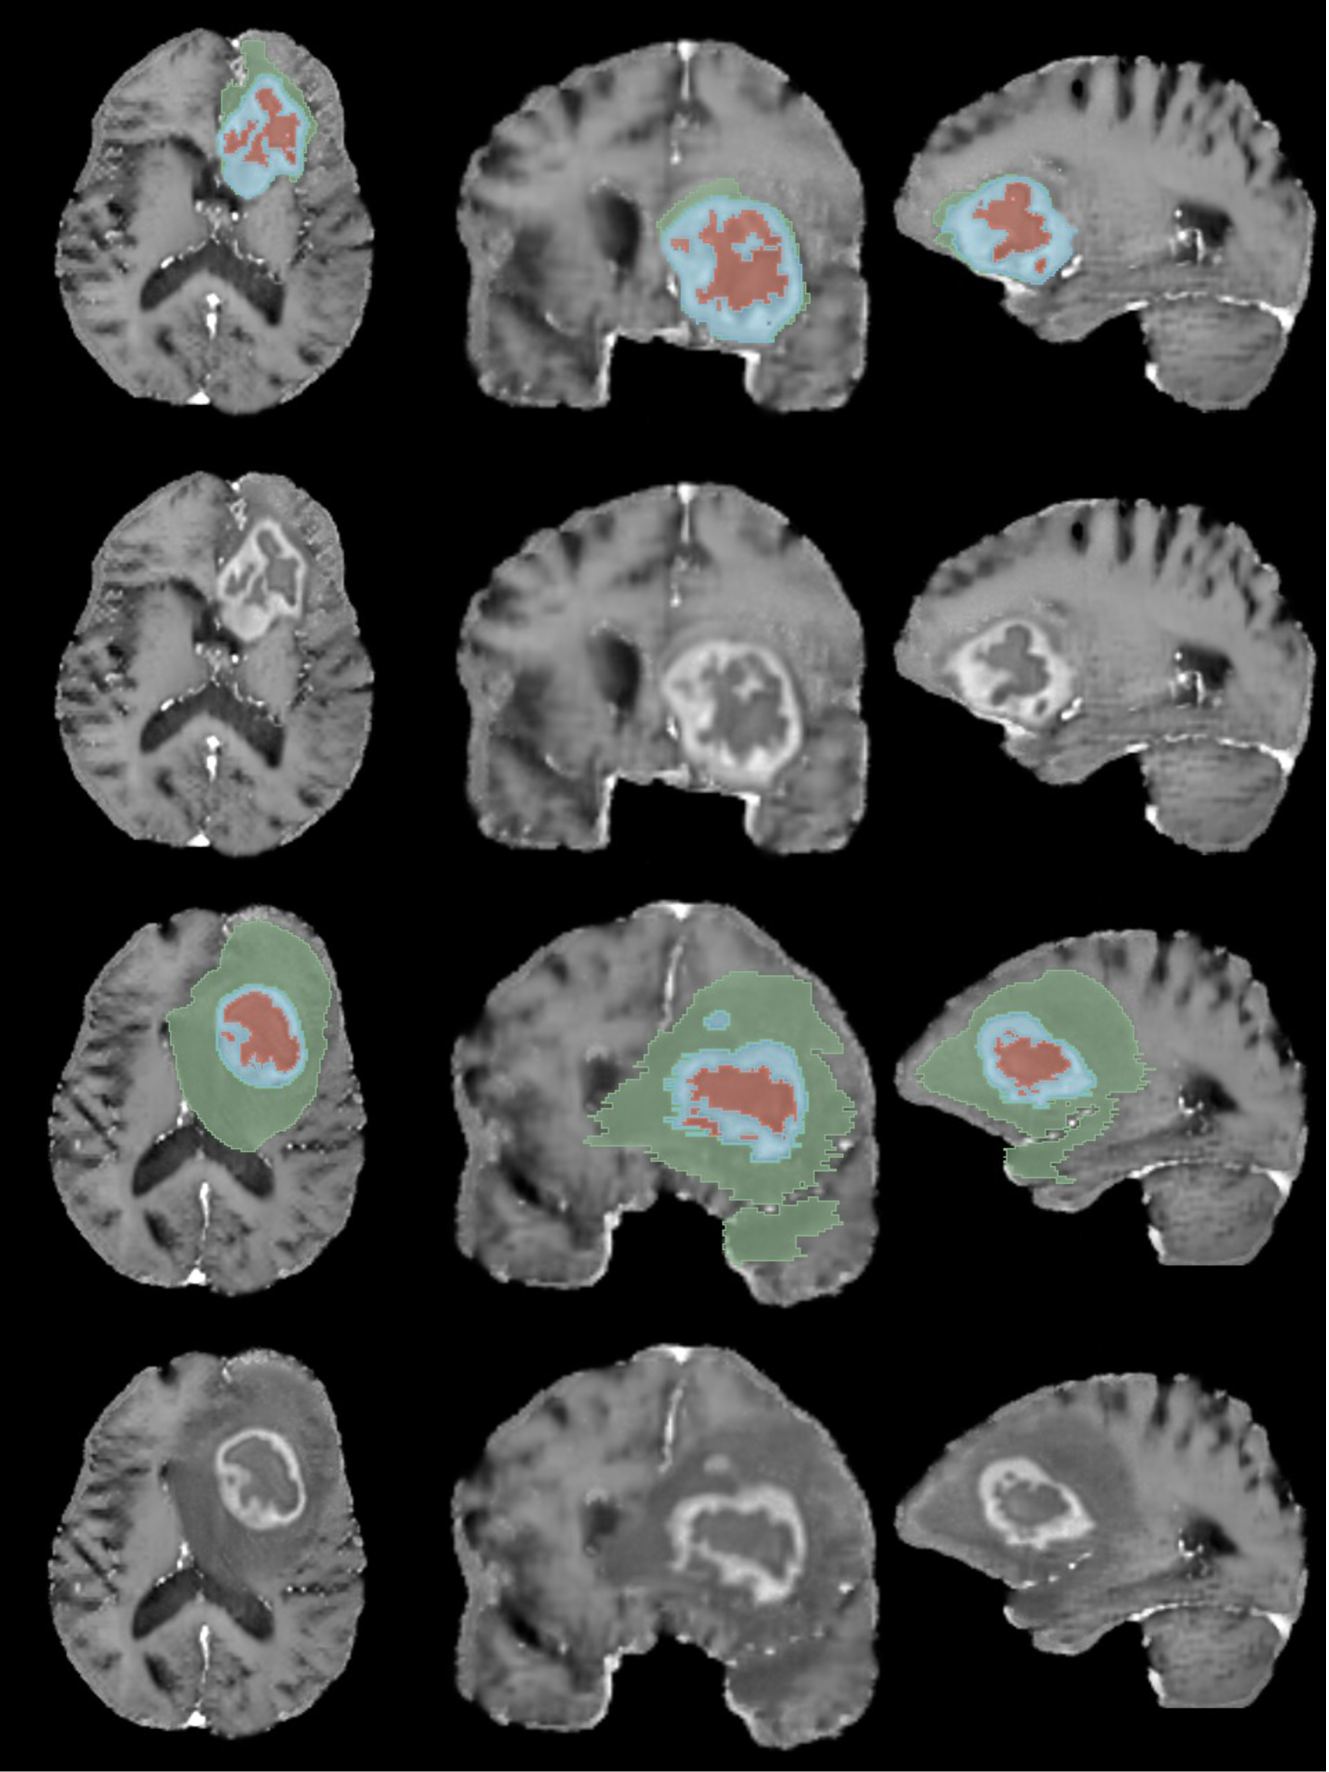

Refer to caption

Figure 2: Visual comparison between real and synthetic samples for both tumor and bone segmentation tasks. Top row: Real cases. Bottom row: Synthetic cases.

Using only synthetic data would improve privacy even further than conventional methods. To this end, we systematically evaluated the feasibility of using solely synthetic data and proposed several techniques to ensure its realism and utility. Accordingly, we focus on the crucial aspect of our research, highlighted in blue in Fig. 1, i.e. the study of the quality of synthetically generated CT and MRI scans using MAE, Multi-Scale Structural Similarity Index Measure (MS-SSIM), Radiomics and a VTT performed by 5 radiologists and their usefulness in segmentation of tumors and bone structures using Dice Similarity Coefficient (DSC). The two leading approaches for synthetic data generation cGANs and conditional DDPMs (cDDPMs) are used [27]. Our objective is to evaluate conditional approaches that facilitate the automatic generation of synthetic data and corresponding ground truth, thereby minimizing the need for specialist intervention and reducing their workload. We also employ two key and inherently time-consuming imaging modalities, MRI and CT, which are routinely used for diagnosis and treatment planning, as well as the segmentation task which is an essential yet labor-intensive task in the medical field, underscoring the need for high-quality results [28]. Fig. 2 illustrates a comparison between samples from the real dataset and synthetically generated with the respective segmentations for each task.

The data was normalized by clipping between the quantiles 0.001 and 0.999 and linearly to the range [-1, 1]. The labels were split into three regions, the Enhancing Tumor (ET), the Tumor Core (TC) composed by the NeCRotic tumor core (NCR), and Peritumoral EDema (ED), and the whole tumor (WT) composed by the three segmentations (NCR+ED+ET). Approximately 80% of the dataset was randomly selected for training (MRIreal1000𝑀𝑅superscriptsubscript𝐼real1000MRI_{\text{real}}^{1000}italic_M italic_R italic_I start_POSTSUBSCRIPT real end_POSTSUBSCRIPT start_POSTSUPERSCRIPT 1000 end_POSTSUPERSCRIPT), and the remaining 20% reserved for testing (MRIreal251𝑀𝑅superscriptsubscript𝐼real251MRI_{\text{real}}^{251}italic_M italic_R italic_I start_POSTSUBSCRIPT real end_POSTSUBSCRIPT start_POSTSUPERSCRIPT 251 end_POSTSUPERSCRIPT). Some examples can be seen in C.

The synthetic datasets were first evaluated by visually inspecting the generated cases followed by Radiomic features mining. We found that the generative networks were better able to capture and reproduce the Radiomic features of MRI scans rather than CT scans. Fig. 3 presents the PCA of Radiomic features extracted from A) tumor region and B) bone region of CT scans, and C) tumor region of MRI scans. Plot C presents a greater overlap and smaller Euclidean distance between real and synthetic pairs than the remaining plots (C=1.08<A=4.06<B=6.79𝐶1.08𝐴4.06𝐵6.79C=1.08<A=4.06<B=6.79italic_C = 1.08 < italic_A = 4.06 < italic_B = 6.79). Considering only the regions to study in the segmentation task, it can be seen that features of synthetic and real tumors present a greater overlap than bone, specially for MRI.

To assess the usefulness of synthetic data, segmentation tests were performed. We found a association between the CCC of Radiomic features and DSC for the segmentation of tumors. CT scans have a poor CCC leading to low performance in the segmentation task (DSC=0.06), in comparison with the real dataset (DSC=0.55). MRI have excellent CCC leading to high performance (DSC=0.83), comparable to the real dataset (DSC=0.89) as illustrated in Fig. 5 A). Moreover, Fig. 5 B) shows that data generated by DDPMs produces better DSC than data generated by GANs.

The segmentation of brain tumors on MRI scans using synthetic cases yielded competitive results compared to using real cases. This task is less challenging than the segmentation of tumors on H&N CT scans, as evidenced by the high DSC of 0.89 achieved by the model trained on real data, as well as the MS-SSIM value of 0.7201, which indicates that the MRI dataset is less variable, making it easier for the generative models to learn the real distribution. Nevertheless, the high DSC achieved by the best model trained on synthetic cases suggests that the synthetic cases exhibit higher fidelity to the real cases, which is supported by the CCC shown in Fig. 4. The segmentation models trained on synthetic data generated by GANs yielded worse results compared to those trained on synthetic data produced by DDPMs. The MS-SSIM of 0.8551 shows that GANs were not able to reproduce the variability of the original MRI dataset. The WT, composed by the ET, NCR and ED, shows the greatest difference between real and synthetic data. This was expectable as the ED contains a hyperintense signal in the FLAIR modality and is more difficult to recognize on the used T1c scans. With a lower contrast difference between the ED and the surrounding tissue, the generative networks had greater difficulty generating this region with higher fidelity, leading to poorer segmentation results. Some synthetic examples can be seen in H. It is also important to notice that the sampling methods ‘DPM++ 2M’ and ‘DPM++ 2M SDE’ show consistently better results than the other methods for all three models. A narrower distribution of cases and a higher similarity between real and synthetic MRI scans recognizable by the high MS-SSIM and low MAE, respectively, are among the main reasons why the generative models were able to better learn the distribution of the MRI data.